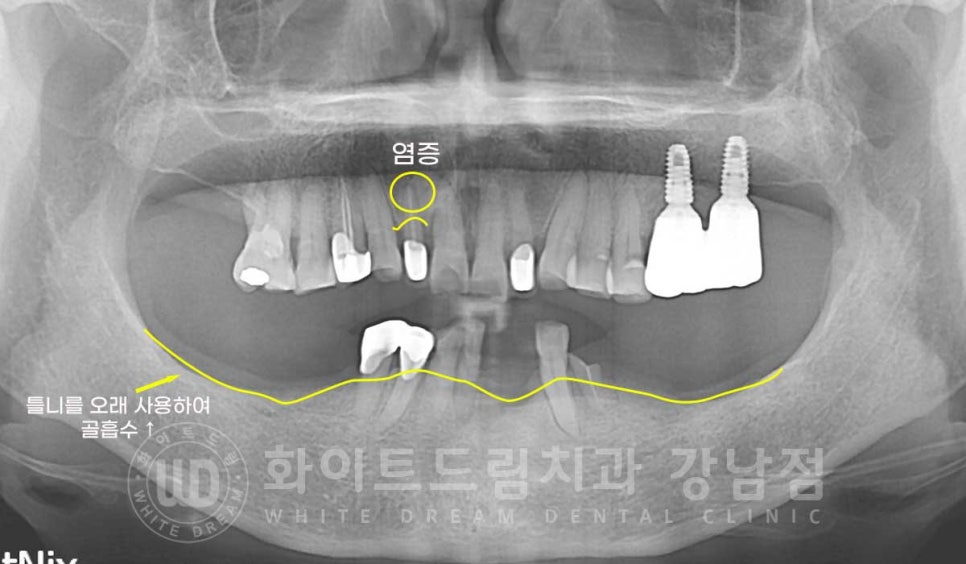

오늘 소개해 드릴 환자분의 초진 사진인데요.

치아가 남아있는 부위는 잇몸뼈가 있고 상실된 치아 부위는 잇몸뼈가 없는 것이 보입니다.

이 부위가 치조골이랍니다.

치아가 상실되면 치조골은 흡수되기 시작하며

틀니를 사용하시는 분들은

틀니가 잇몸을 누르는 압박으로 인해 치조골 흡수가 가속화되어 일어납니다.

잘 제작된 틀니여도 유지관리 없이 장기간 사용한다면 잇몸을 누르는 압박으로 인해

잇몸뼈 흡수는 더욱 빨라지게 된답니다.

오늘 소개해 드릴 치료 환자분은 틀니를 오랜 시간 사용하셔서

잇몸뼈가 굉장히 얇은 상태로 거의 점막만 남아있는 상태의

환자분입니다.

하악 부분틀니 10년 정도 꼈는데

이제는 뺏다 꼈다 하는 것도 힘들고 불편해요

임플란트로 치료를 받고 싶은데 가능할까요?

상악 염증으로 흔들리는 12번 치아도 함께 치료를 진행하기로 했는데요.

하악 임플란트는 하악 턱뼈 안을 지나가는 신경을 항시 주의하며

치료를 진행해야 합니다.

치조골이 흡수되면서 신경관과의 거리도 가까워지기에

사전에 3D-CT를 통해 위치를 정확하게 확인한 후 치료에 들어가게 됩니다.